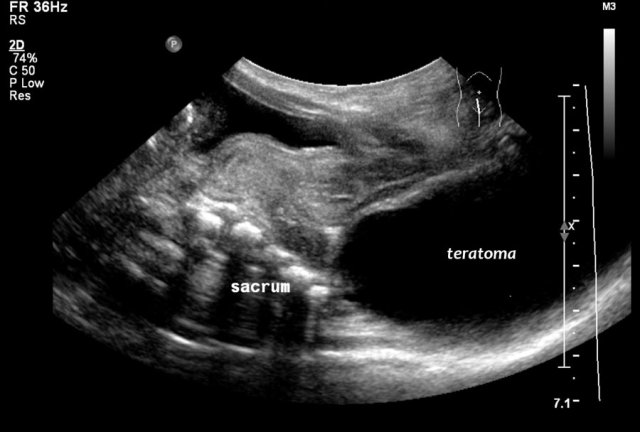

Two-year-old girl with a sacral mass. On ultrasound a cystic lesion anterior to the sacrum is seen, compatible with a class 4 sacrococcygeal teratoma. It was completely resected.

The intraspinal extension was visible on ultrasound, but MRI provides a better overview and a document for future comparison.

A parasagittal MRI shows a presacral cystic mass.

Newborn girl with a sacrococcygeal teratoma with external and internal solid and cystic parts, and a large intraspinal extension.